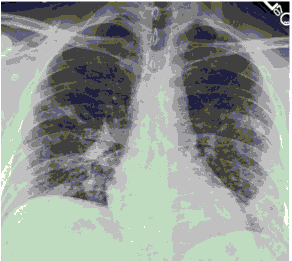

Стандартная РГ имеет низкую чувствительность в выявлении начальных изменений в первые дни заболевания и не может применяться для ранней диагностики. Информативность РГ повышается с увеличением длительности течения пневмонии. Рентгенография с использованием передвижных (палатных) аппаратов является основным методом лучевой диагностики патологии ОГК в ОРИТ. Применение передвижного (палатного) аппарата оправдано и для проведения обычных РГ исследований в рентгеновском кабинете. В стационарных условиях относительным преимуществом РГ в сравнении с КТ являются большая пропускная способность. Метод позволяет уверенно выявлять тяжелые формы пневмоний и отек легких различной природы, которые требуют госпитализации, в том числе направления в ОРИТ.

5. Рекомендовано проведение лучевого исследования пациентам при среднетяжелом, тяжелом и крайне тяжелом течении ОРИ с целью медицинской сортировки, оценки характера изменений в грудной полости и определения прогноза заболевания:

- выполнение КТ легких без внутривенного контрастирования в стационарных условиях или в амбулаторных - при показаниях к госпитализации;

- выполнение РГ легких в двух проекциях, если проведение КТ в данной медицинской организации/клинической ситуации невозможно.